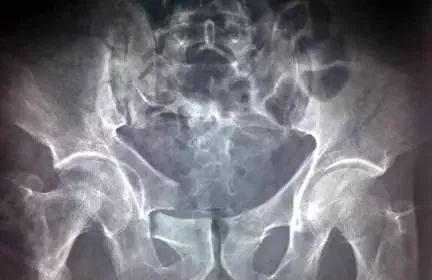

图1 骨盆正位片

(1)髋骨的X线解剖 常规投照正位(图1)。在X线像上,构成髋骨的三个部分融合于髋臼,可清晰分辨。髂骨翼的内侧1/4影像与骶骨影像重叠,外侧3/4因有髂窝而较透亮。髂嵴阴影较致密,边缘不光滑,外侧可见髂前上棘影,髂后上棘则重叠于骶骨影内。弓状线及骨盆腔内侧壁形成复合影像,外侧可见弧形的髋臼阴影。髋臼阴影的上段粗而致密,中段较细,它向下绕过髋臼切迹前部的下缘,与耻骨体的内面形成一条“U”形的致密线,称为泪滴线(Koekler泪滴),泪滴线二脚之间的距离,即髋臼窝的厚度。髋臼内下方的透亮影为闭孔。闭孔影的上界是耻骨上支、外侧界是坐骨体的下份,坐骨结节阴影与其重叠。坐骨棘的阴影呈三角形突向盆腔。

(2)骨盆的X线解剖 骨盆一般投照前后位,检查骶、尾骨时可加照侧位,检查骶髂关节时应加照45°斜位,产科骨盆测量另有其特殊投照方法。骨盆前后位片上,骶骨中线应通过耻骨联合。骶髂关节左右对称,关节间隙下半部分可以显示,上半部常投影出模糊双线影。界线的影像在女性呈卵圆形,在男性略呈鸡心形。髂嵴连线影正好通过第4、5腰椎间隙。由髂嵴影向外可追踪到骼前上、下棘,由髂前下棘到股骨颈外上缘的连线称髂颈线,用以判定髋关节是否正常。正位片上,可以测量耻骨下角,男性为锐角,女性为钝角。

女性骨盆径线的测量,可以采用正位(见图1)和侧位。正位片上,界线影像最远点连线为入口横径,正常为12.3cm;两侧坐骨棘连线为中骨盆横径,正常为10.5cm;两侧坐骨结节间距为小骨盆出口横径,正常为11.8cm。侧位片上,耻骨联合后缘上端到骶骨岬连线为小骨盆入口前后径,正常为11.6cm;耻骨联合后缘下端和坐骨棘中点的连线延长到骶骨的前缘,为中骨盆前后径,正常12.2cm;耻骨联合后下缘到骶尾关节的连线,为小骨盆出口前后径,正常11.8cm。

(3)髋关节的X线解剖 常规拍摄正位(见图1)和侧位X线片。正位线片上,因髋臼三骨之间以“Y”形软骨相连,融合之前,表现为横行带状透亮影,其宽窄随着年龄变化而改变。年龄越小此透亮带越宽;年龄越大,透亮带变窄,15~17岁左右消失。股骨头大部套在髋臼内,表面光滑,为致密的细弧线。头的中心偏后下部有一小凹陷,是股骨头凹,有时可投影到股骨头弧线内侧,显示为小环形透亮圈。侧位片上,中央的凹窝是髋臼,呈半圆形的致密线。